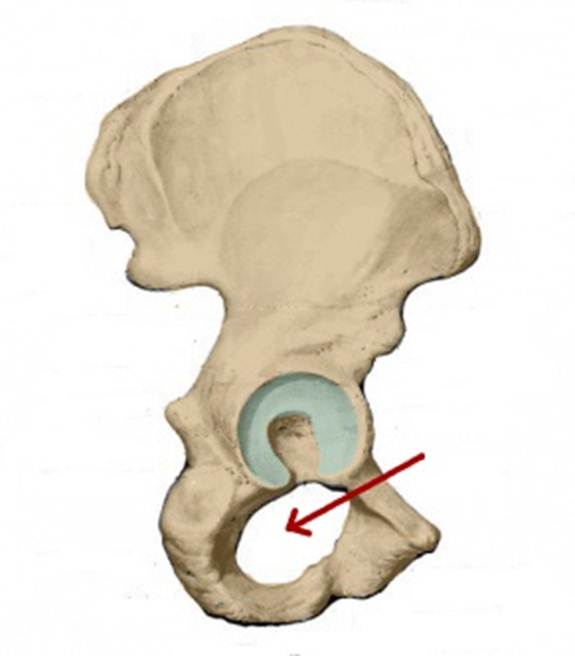

S: Стрелка указывает на facies lunata (латинский язык).

S: Стрелка указывает на incisura acetabuli

S: На рисунке обозначен art. Coxae (латинский язык).

I:

S: Стрелка указывает на zona orbicularis

I:

S: Стрелка указывает на lig. Ischiofemorale

I:

S: Стрелки указывают на lig. iliofemorale

I:

S: Стрелка указывает на lig. pubofemorale

I:

S: Стрелка указывает на labrum acetabuli

I:

S: Стрелка указывает на lig. Capitis femoris

I:

S: Стрелка указывает на facies lunata